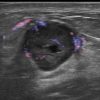

Ung thư vú

Ung thư vú - Ảnh 2

» Thông tin: Nữ giới – 54 tuổi.

» Lâm sàng: Khối tuyến vú.